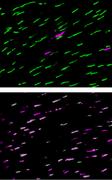

Fluoreszenzmikroskopische Aufnahmen der Zapfenzellen in der Retina einer erwachsenen gesunden Ratte (oben) und einer erwachsenen hypothyreoten Ratte (unten). Die Zapfentypen wurden mit Antikörpern gegen die Opsine angefärbt, das Grün-Opsin ist grün und das UV/Blau-Opsin purpur dargestellt. Die gesunde Ratte besitzt viele Grünzapfen und wenige UV/Blau-Zapfen. Eine Abnahme des Schilddrüsenhormonspiegels führt zur Bildung von UV/Blau-Opsin in allen Zapfen und der Abnahme von Grün-Opsin. Die heller purpur erscheinenden Zapfen im unteren Bild sind solche, die neben viel UV/Blau-Opsin auch etwas Grün-Opsin enthalten. Martin Glösmann